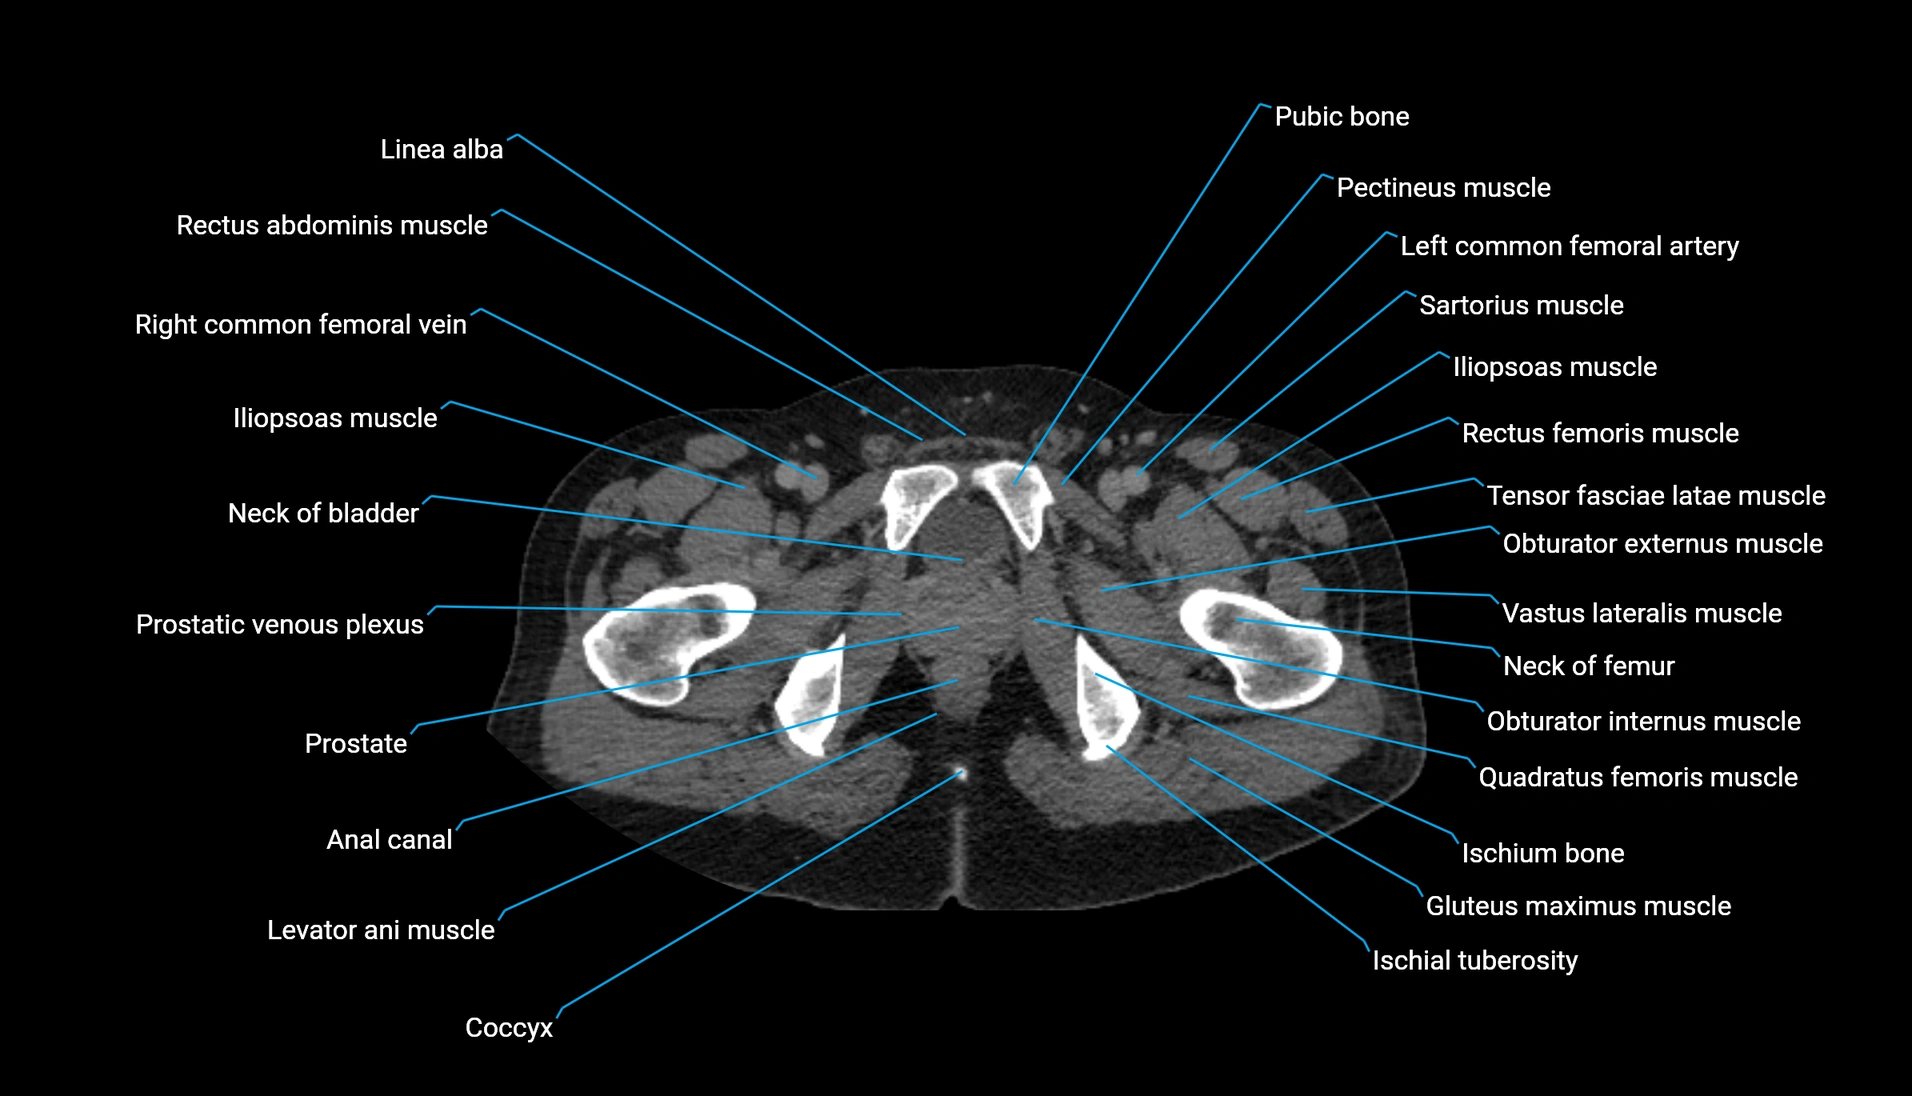

CT Appearance

Non-contrast CT:

-

Demonstrates cortical bone of acetabular rim in excellent detail

Detects fractures, dysplasia, retroversion, or bony overcoverage (pincer impingement)

3D reconstructions used in preoperative hip surgery planning

CT VRT 3D image

CT image